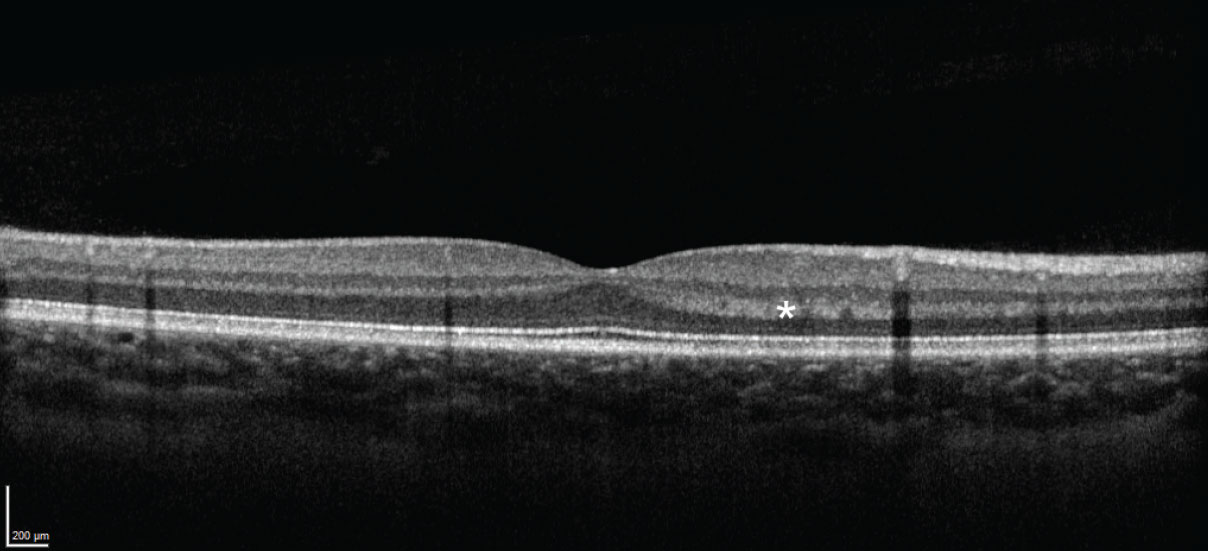

The HFL can appear hyperreflective due to alterations in either: 1) the angle of incident light or 2) the structure of the HFL itself.5,6 The first can occur due to slight variations in the orientation of the patient’s eye or changes in the orientation of the retina itself, such as with subretinal or sub-RPE pathology (Figure 3).4 The second can occur when material, such as hemorrhage or exudate, accumulates in the HFL, or when the HFL itself is disrupted.

Figure 3. Normal OCT image from a different eye, demonstrating hyperreflectivity of the Henle fiber layer resulting from the orientation of the incident light. |